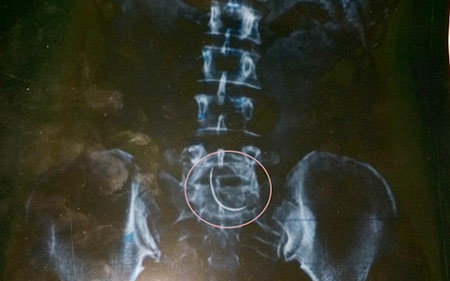

Hình ảnh chiếc kim khâu cong vút từ phim chụp X-quang của chị Hòa.

Thế nhưng, để chắcchắn, ngày 5/11, anh Tiến lại đưa vợ ra BVĐK Cửa Đông (TP Vinh, Nghệ An) kiểmtra. Nhận kết quả phim chụp từ tay bác sĩ, anh Tiến và chị Hòa không tin vào mắtmình, hình ảnh một chiếc kim cong vút nằm ở vùng bụng chị Hòa.

"Tôi thực sựkhông biết vì sao chiếc kim khâu lại nằm trong bụng mình. Hơn nữa nó lại nằm ởchỗ vết thương mà trước đây các bác sĩ tại BVĐK Can Lộc tiến hành mổ. Nhìn phimchụp mà tôi sởn gai ốc", chị Nguyễn Thị Hòa nhớ lại.

Chiếc kim đócong cong như lưỡi câu cá, có độ dài chừng 3-5cm. Nghĩ tới đó thôi là cả ngườitôi ớn lạnh, chị Hòa rùng mình nói.